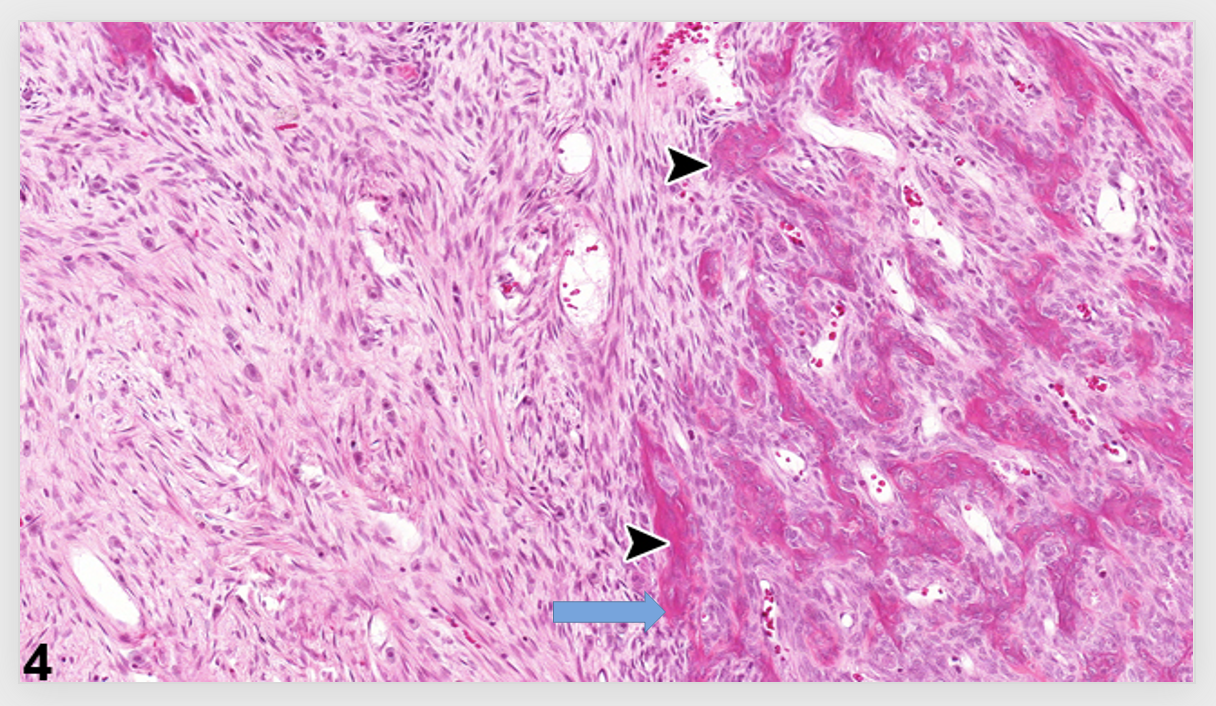

Cement lines in bone

The cement line, which is the interface between the ‘fibers’ (osteons) and extraosteonal bone matrix, may impart important mechanical properties to compact bone.

Arche sof bone - periosteal reaction form inner cambium layer - benign